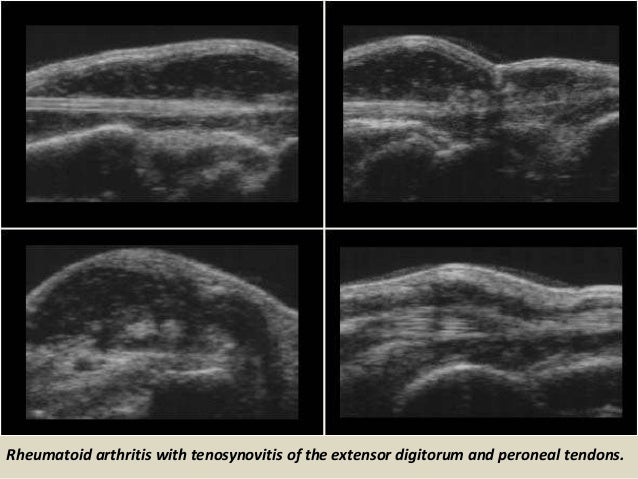

Rheumatoid arthritis with tenosynovitis of the extensor digitorum and peroneal tendons.

40. 40. Rheumatoid arthritis with tenosynovitis of the extensor digitorum and peroneal tendons.